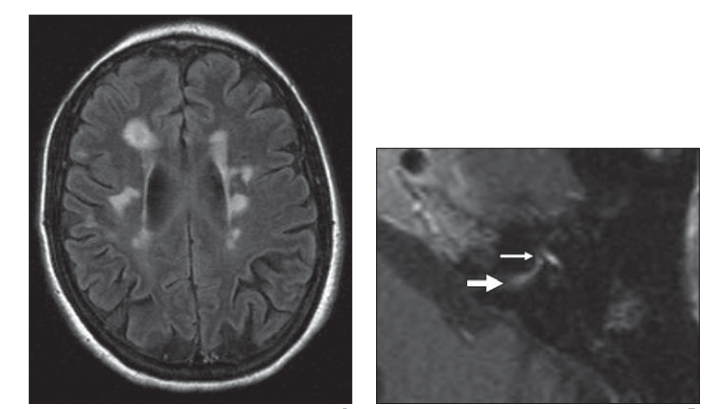

图5,多发性硬化

患者,左:FLAIR;右:T1增强,面神经迷路段异常增强,膝状神经节正常增强

图6,T1增强,慢性炎性脱髓鞘多神经病患者右侧迷路段、膝状神经节异常增强,可以看到右侧膝状神经节信号较左侧明显